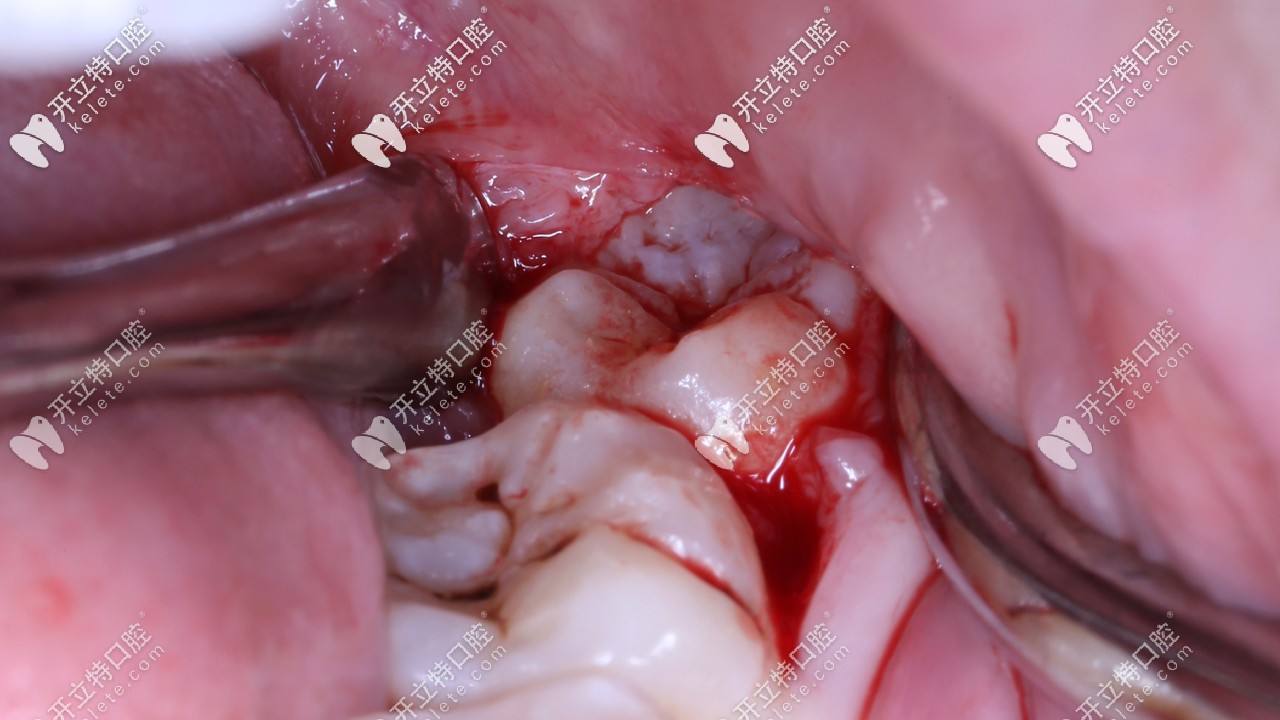

但是像我這長(zhǎng)出一半,一半被肉包著,容易發(fā)生齲壞,而且反復(fù)感染痛疼,就需要拔除,像我這樣的需要切開齦瓣,當(dāng)時(shí)聽醫(yī)生這么說(shuō),真的感覺挺恐怖,??谖⑿谇蛔o(hù)士姐姐一再安慰我,拔牙是打麻藥的,拔的時(shí)候是感覺不到痛的。

打麻藥的時(shí)候有一點(diǎn)酸疼,針會(huì)直接插進(jìn)牙齦里。等了10分鐘左右麻藥很快就產(chǎn)生效果,整個(gè)右半邊臉是麻的,我特意用指甲使勁掐了下嘴唇,一點(diǎn)都不疼,麻藥起作用后就開吃拔牙,我都不知道什么時(shí)候牙齦被掀開,拔牙的時(shí)候用的鉗子,牙挺,錘子,不過(guò)沒敲幾下就聽到醫(yī)生說(shuō)已經(jīng)松了,整個(gè)過(guò)程張著嘴,無(wú)感覺,男醫(yī)生力氣大,一拔就出來(lái)了。